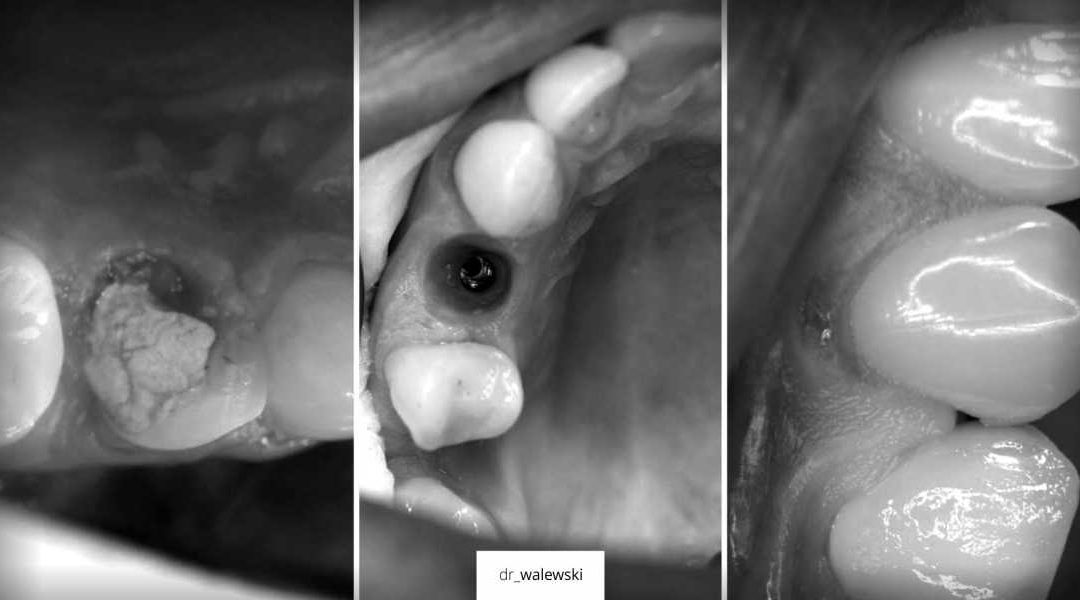

Po urazowe złamania zęba natychmiastowa implantacja by dr_walewski

W wyniku urazu, doszło do złamania zęba 14, natychmiastowa implantacja i odbudową protetyczną